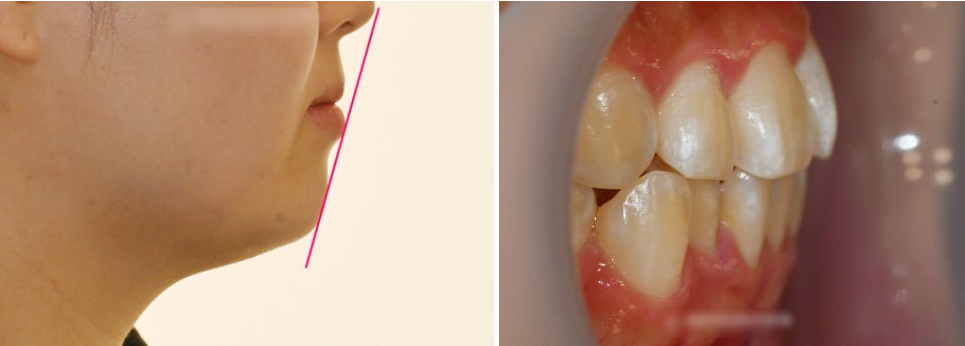

면목역 치과 에서 진행한 구강 검진에서는

특히 전치부를 주목해서 볼 필요가 있습니다.

위아래 측절치들이 하나씩 안으로 들어간 듯한

총생의 양상을 보여주고 있습니다.

동시에 정중성이 일치되지 않는

양상들도 보여주고 있습니다.